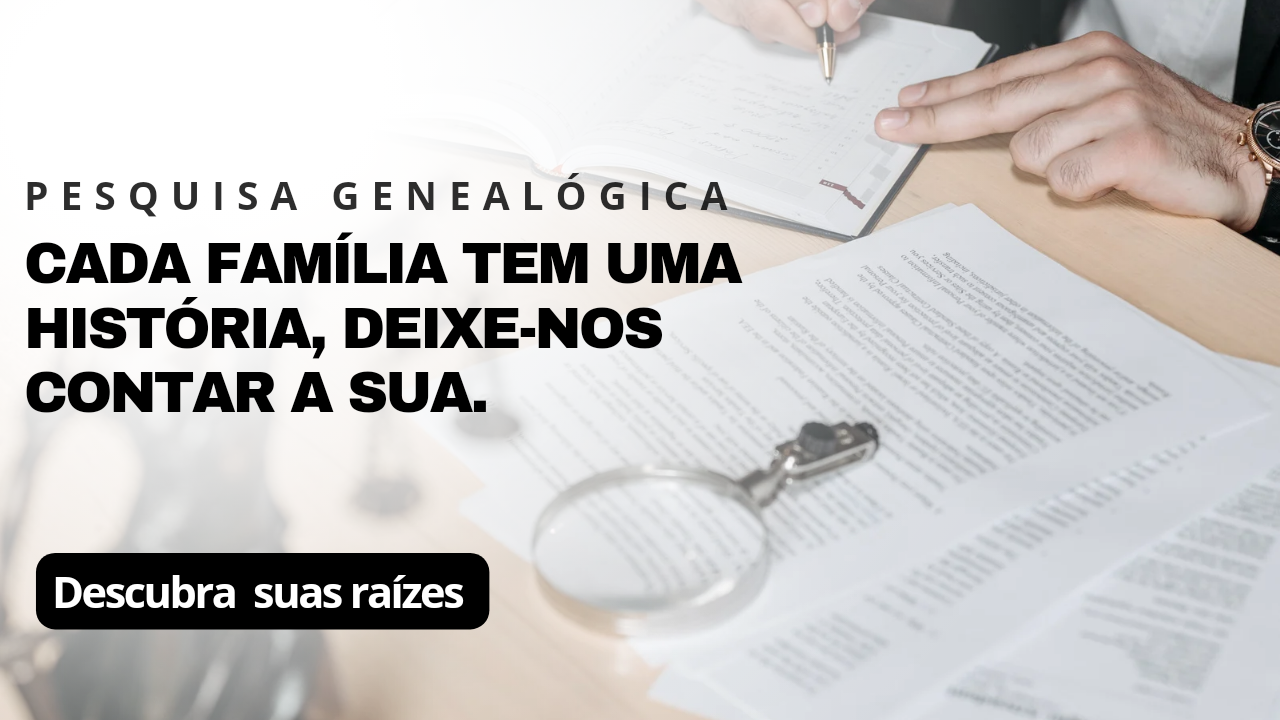

Para quem acompanha a paisagem do câncer pulmonar, esses números são como um novo broto na terra: pequenos, mas promissores. Como lembra o oncologista Federico Cappuzzo, diretor de Oncologia Medica 2 do Istituto Nazionale Tumori Regina Elena, em Roma, o carcinoma pulmonar causa mais de 44.800 novas diagnósticos por ano na Itália; o subtipo a pequenas células, também chamado de microcitoma, corresponde a cerca de 15% desses casos. É uma neoplasia feroz, intimamente ligada ao tabagismo, e na maioria das vezes já se apresenta em estágio extenso no momento do diagnóstico (aproximadamente 70%–80% dos casos).